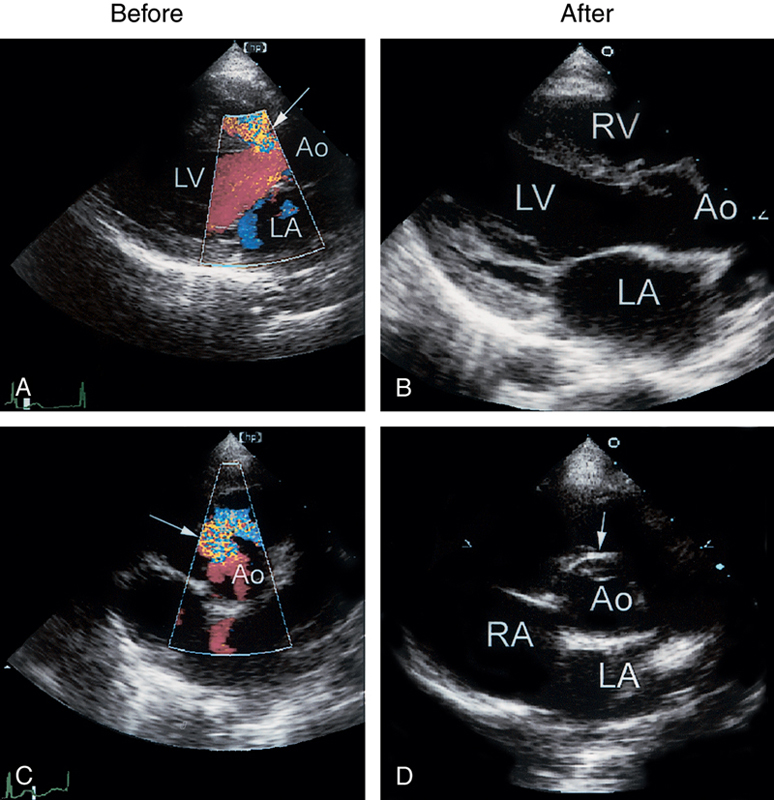

فحوصات تشخيصية لبعض امراض القلب والشرايين التاجية